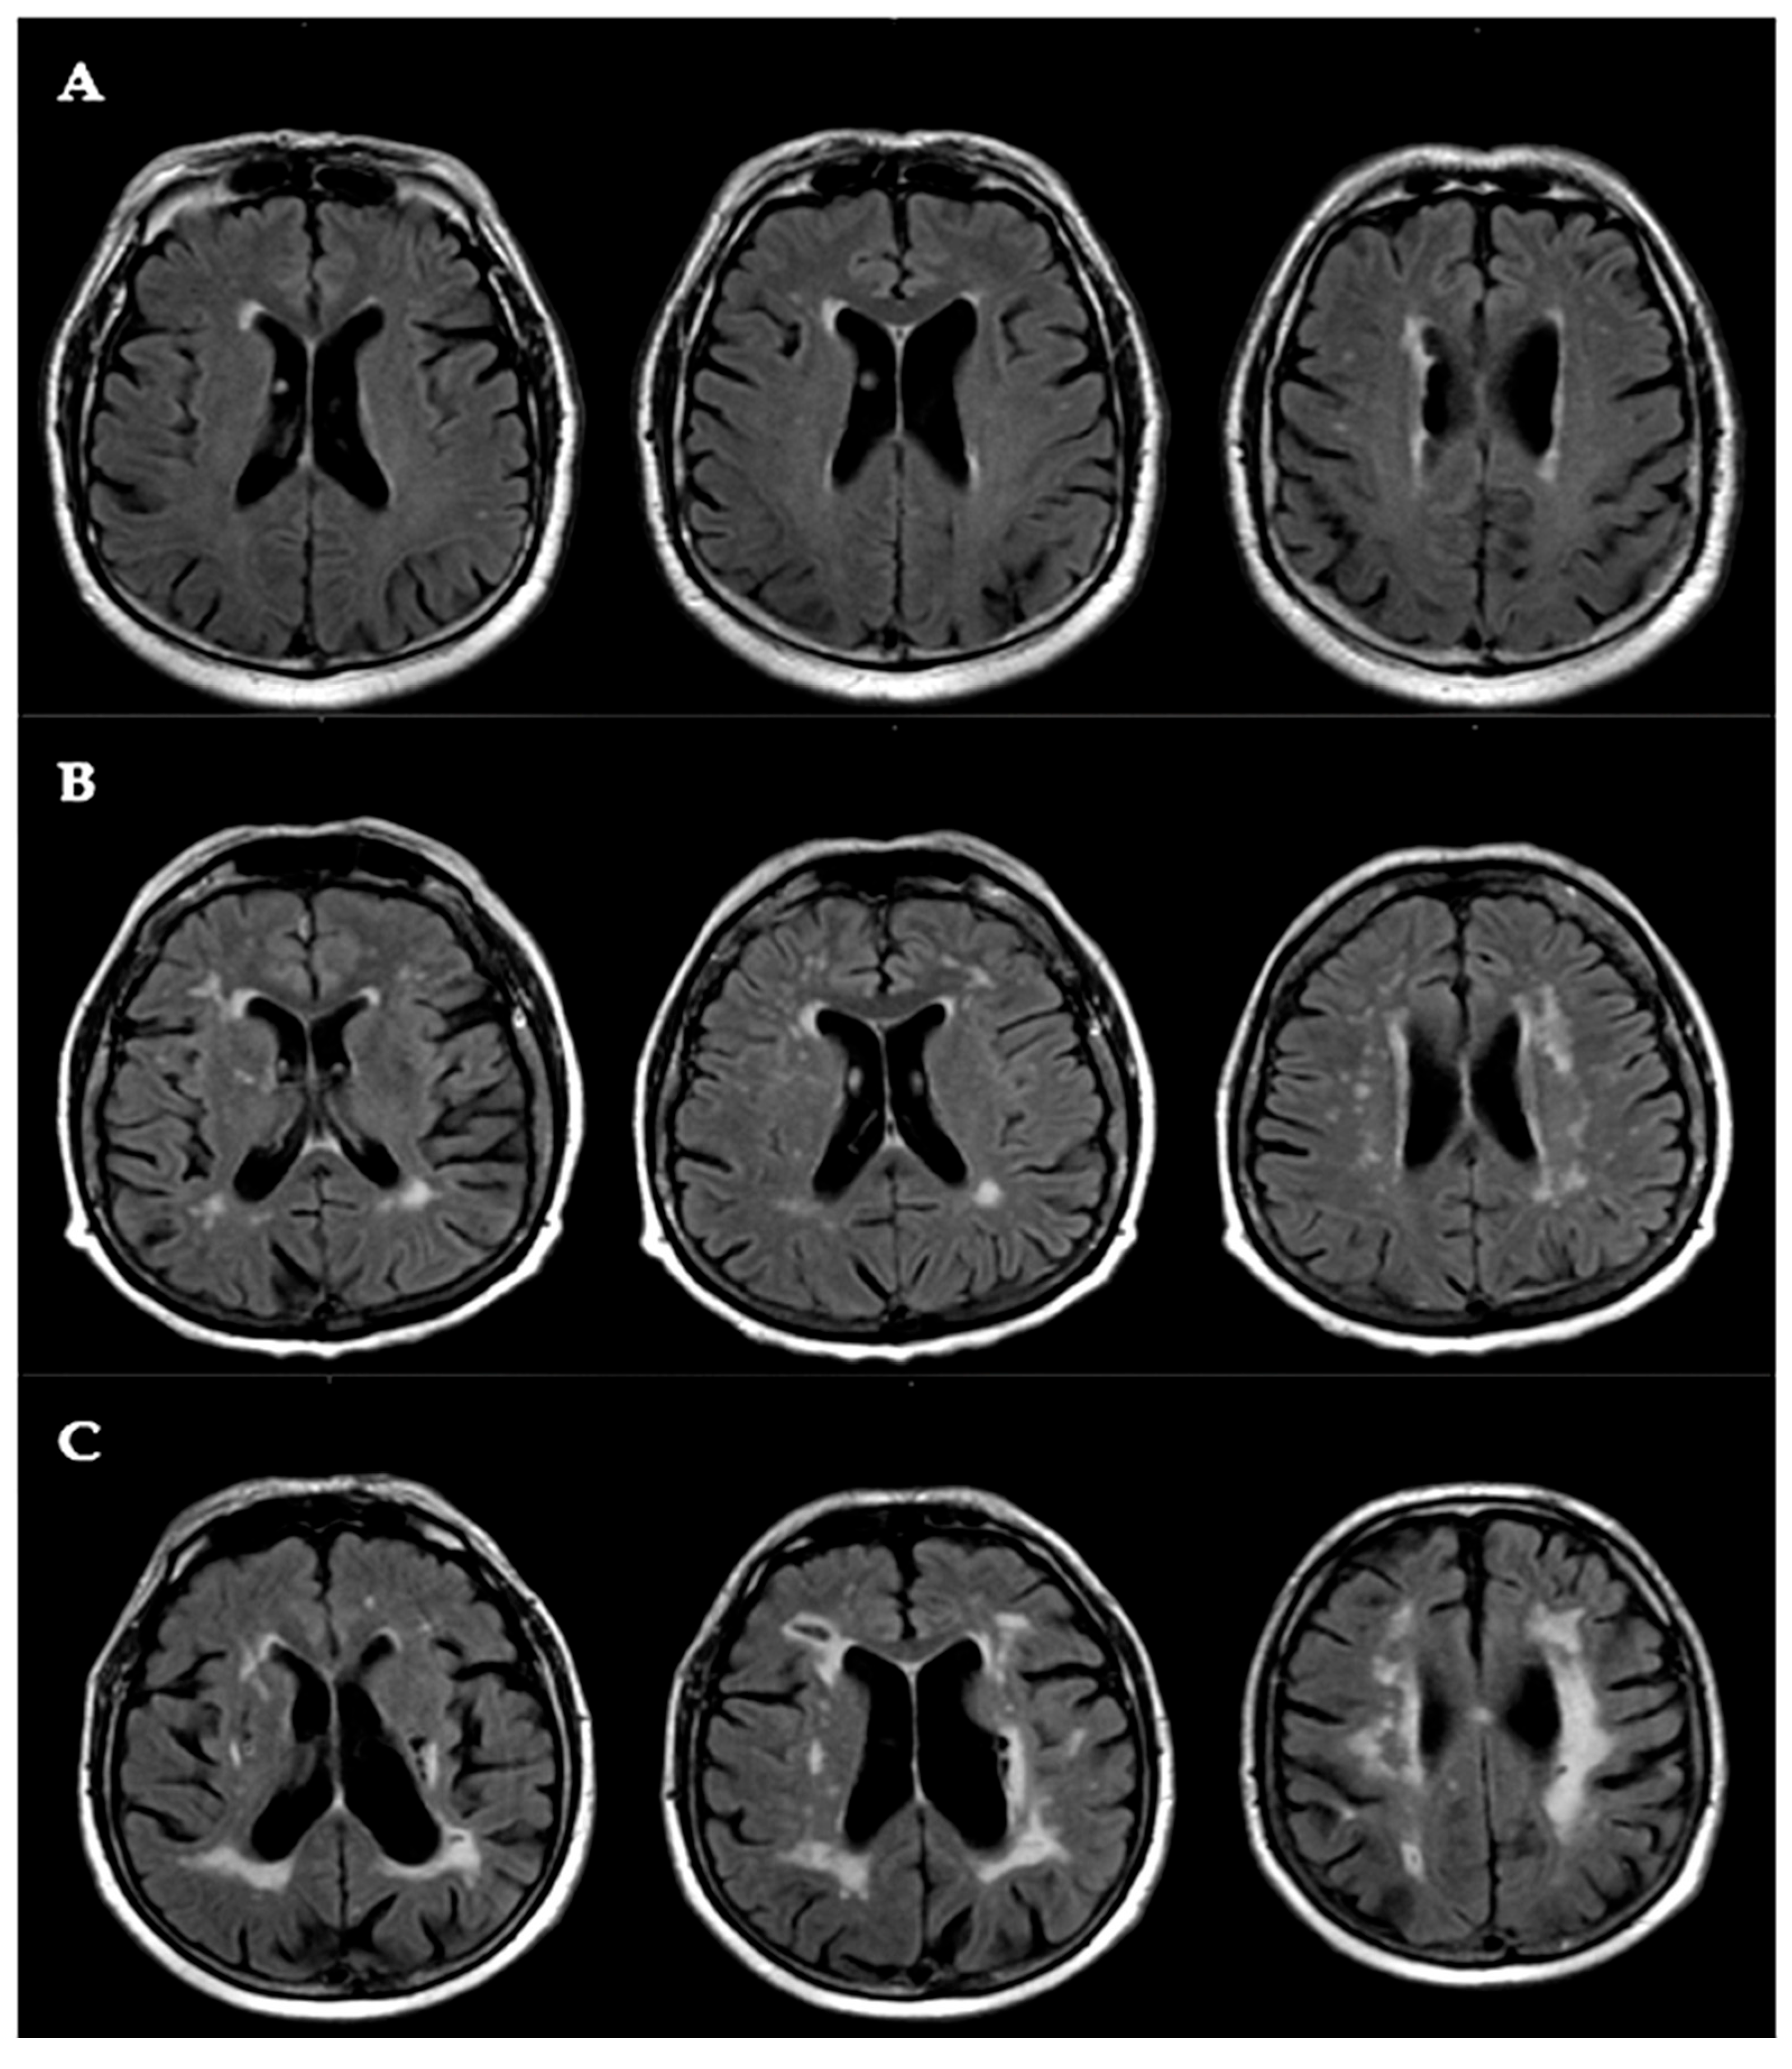

2.5. White Matter Lesion (WML) Assessment

| MRI Fazekas visual scale | 2.0 (1.0–3.0) | 3.0 (2.0–3.0) | 2.0 (1.0–3.0) | 0.03 |

| Grade 1 n (%) | 27 (35) | 3 (17 | 30 (31) | 0.14 |

| Grade 2 n (%) | 30 (38) | 5 (28) | 35 (37 | 0.42 |

| Grade 3 n (%) | 21 (27) | 10 (55) | 31 (32) | 0.02 |